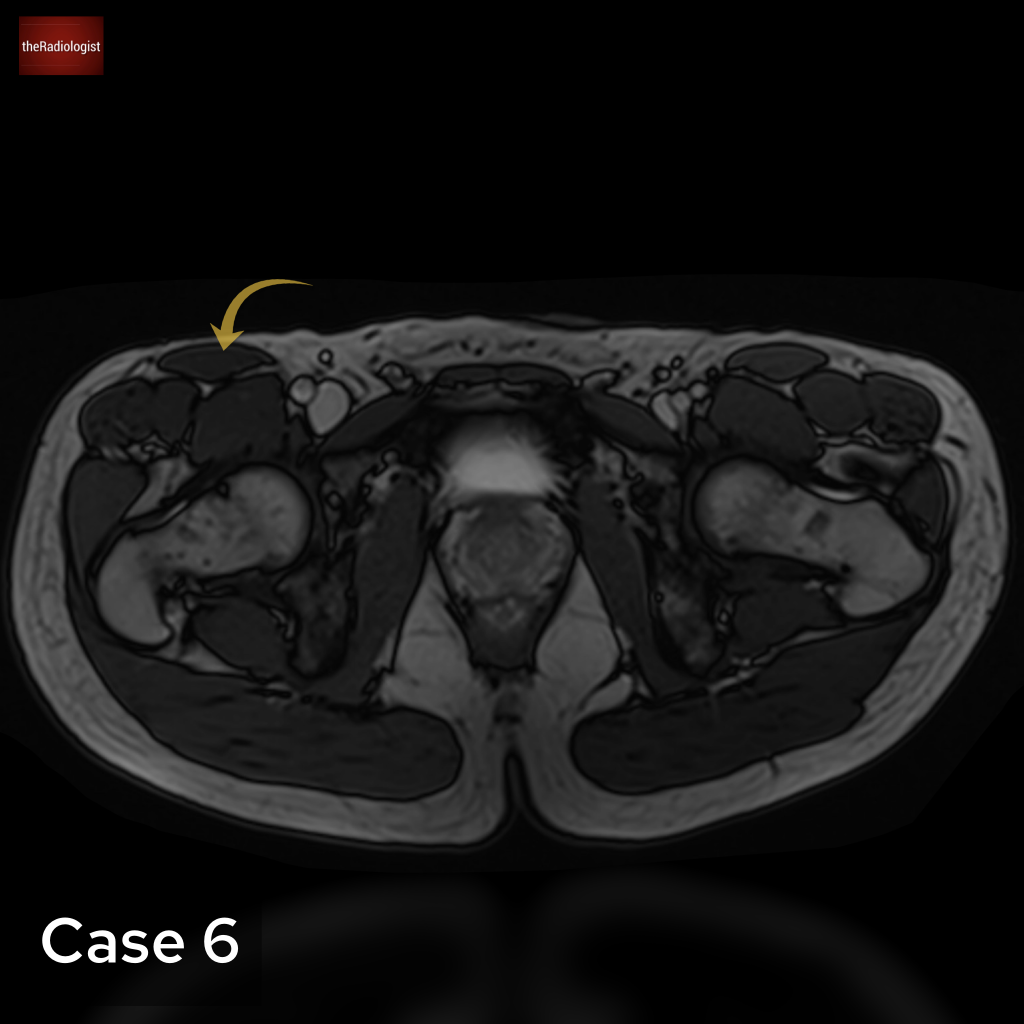

Case 6

Another MRI, this time we’re going down to the pelvis. What is the arrow pointing at?

Choose from one of the following options: